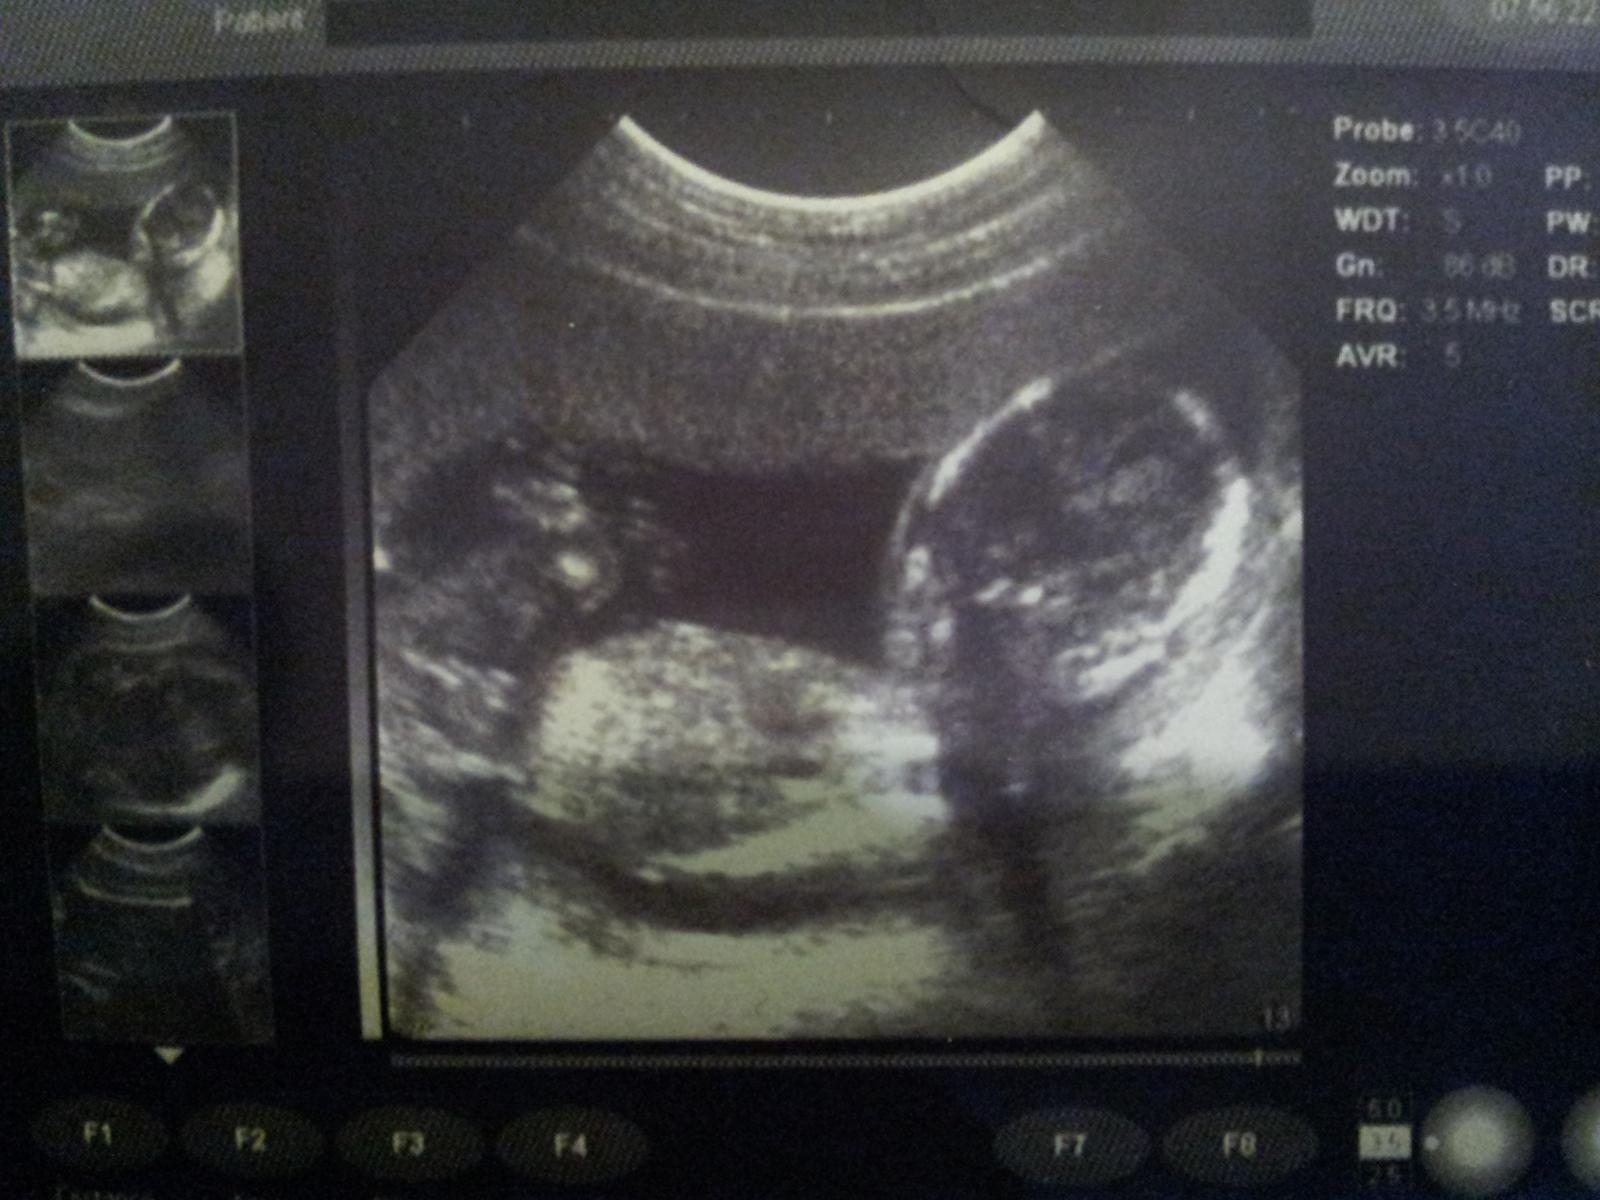

dnes mi urobil doky fotky maleho/malej. Nelubi sa fotit 🙂 To ma po mamke 🙂

A takto to vyzera zvonka 😉